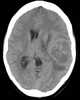

Metastasis from leiomyosarcoma

Leiomyosarcoma, is a malignant (cancerous) smooth muscle tumor. A benign tumor originating from the same tissue is termed leiomyoma. [Source: Wikipedia ]